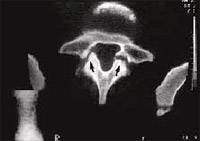

Fig. 3 – Tomografia axial computadorizada do paciente da figura 1. Nível pedículo de L5 mostrando fratura do anel apofisário (seta maior) e da placa superior de L5 – nódulo de Schmorl – (seta menor). |